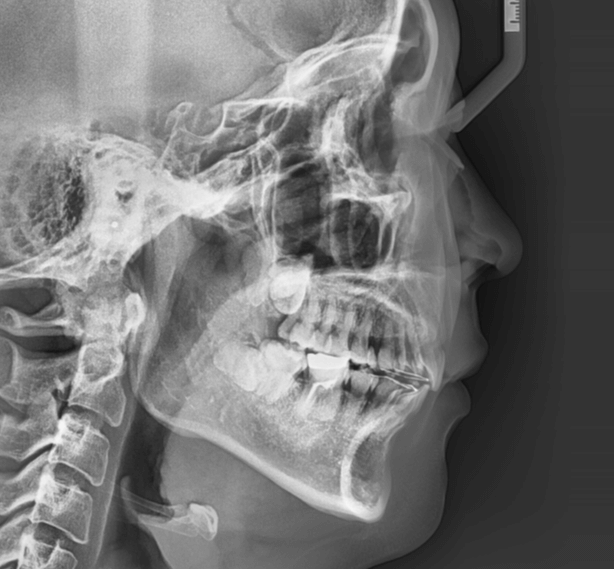

| 年齢・性別 | 25歳女性 |

|---|---|

| 主訴 | 前歯の歯並びの乱れ(叢生)を気にされて来院された。咬み合わせや審美的な改善を希望されていました。 |

| 治療期間・回数 | 4年5ヶ月・30回 |

| 費用 | 1100,000円(税別) |